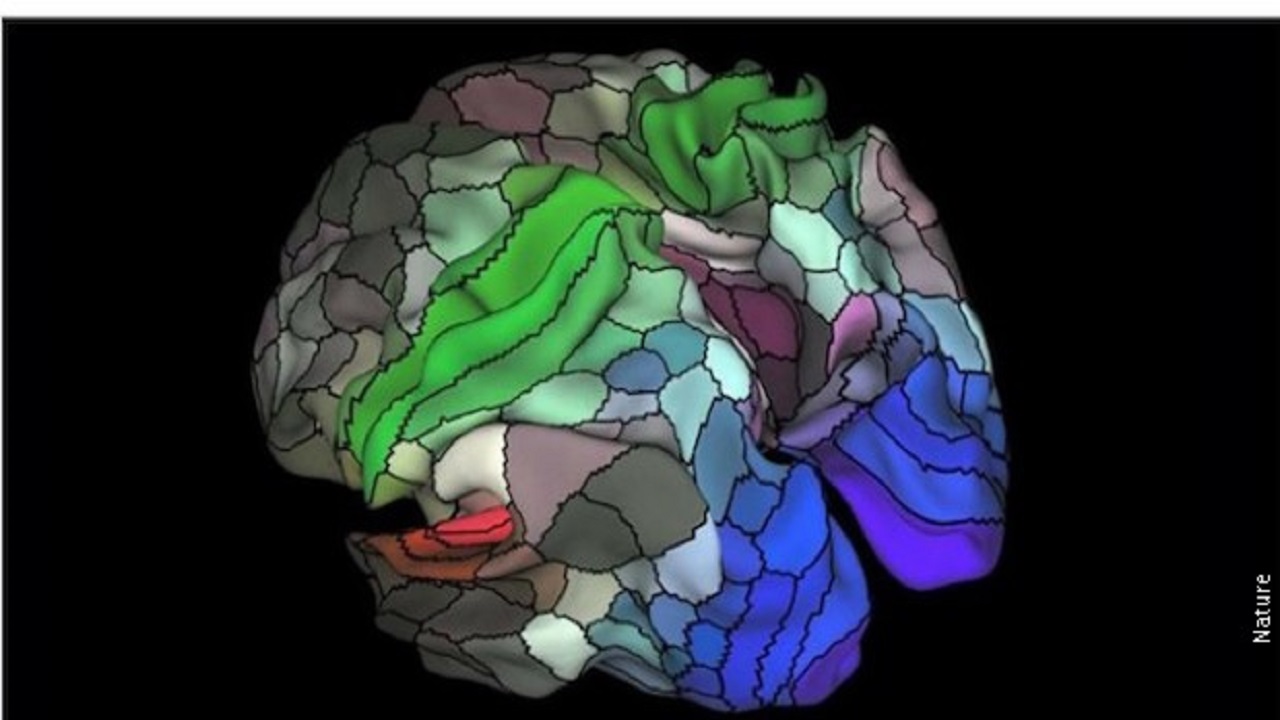

Хантингтонова болест

Хантингтонова болест je ретка, хронична, неуродегенеративна болест мозга. То значи да нервне ћелије у вашем мозгу временом пропадају. Болест обично почиње између 30. и 50. године, али може почети и раније.